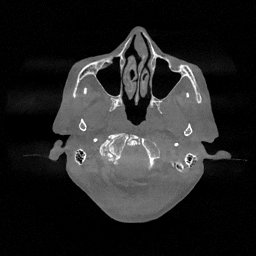

III-D Real Clinical Data Experiment

The experimental results on clinical head data are shown in Fig. 4. The reference images were reconstructed using the fast iterative shrinkage-thresholding algorithm (FISTA) with total variation regularization from non-truncated projection data. In the WCE reconstructions (Fig. 4(b)), severe truncation prevents accurate recovery of anatomical structures outside the FOV. Despite being trained solely on simulated data with a domain gap, all deep learning models can restore a substantial portion of the missing anatomy. Among them, the diffusion-based methods recover soft-tissue boundaries more faithfully than the conventional deep learning approach FBPConvNet, highlighting their stronger image generation capability. However, cDDPM reconstructions exhibit more noticeable noise than those from other methods, consistent with the simulated data results. The patchDiffusion model introduces artifacts within the FOV, likely due to its patch-wise processing strategy. While I2SB shares the same limitations as other diffusion models in perfectly restoring soft-tissue detail, it produces fewer residual noise patterns and fewer artifacts within the FOV boundaries. Overall, Fig. 4 demonstrates the strong efficacy of I2SB in reconstructing real CBCT data.